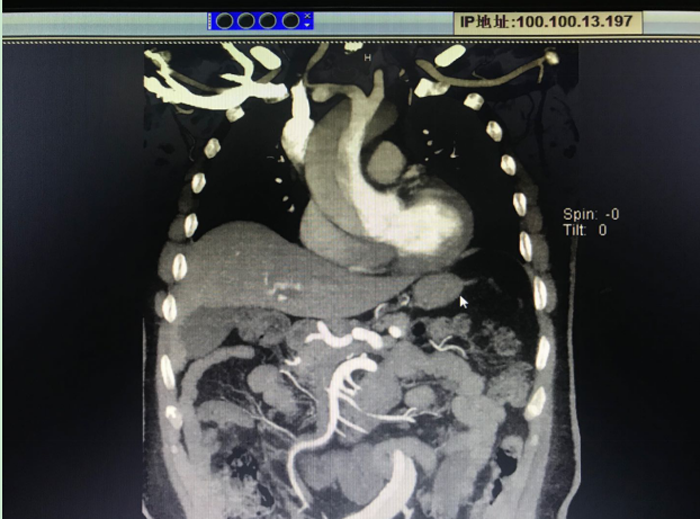

患者術(shù)前CT

患者男,48歲,因持續(xù)胸背部疼痛不適1小時(shí)來我院急診就診,急診行主動(dòng)脈CTA檢查,確診為主動(dòng)脈夾層(Stanford A型)。醫(yī)生告知患者家屬,患者病情危重,需要盡快手術(shù)治療才有生的希望。但棗莊地區(qū)從未開展過這種“超級(jí)手術(shù)”,以往這種情況都只能轉(zhuǎn)到濟(jì)南、北京、上海等大醫(yī)院手術(shù),并且不少患者在轉(zhuǎn)運(yùn)過程中因夾層破裂導(dǎo)致死亡?;颊卟∏槲V?,家屬擬轉(zhuǎn)上級(jí)醫(yī)院行手術(shù)治療。但由于患者動(dòng)脈夾層累及右冠狀動(dòng)脈,右冠狀動(dòng)脈根部撕裂,心包大量積血,患者生命體征不平穩(wěn)血壓降至58/30mmHg,不宜轉(zhuǎn)運(yùn)。為此,全院高度重視,隨即聯(lián)系山東大學(xué)齊魯醫(yī)院龐新焱教授來我院協(xié)助進(jìn)行升主動(dòng)脈+主動(dòng)脈弓人工血管置換+降主動(dòng)脈象鼻支架置入術(shù)。